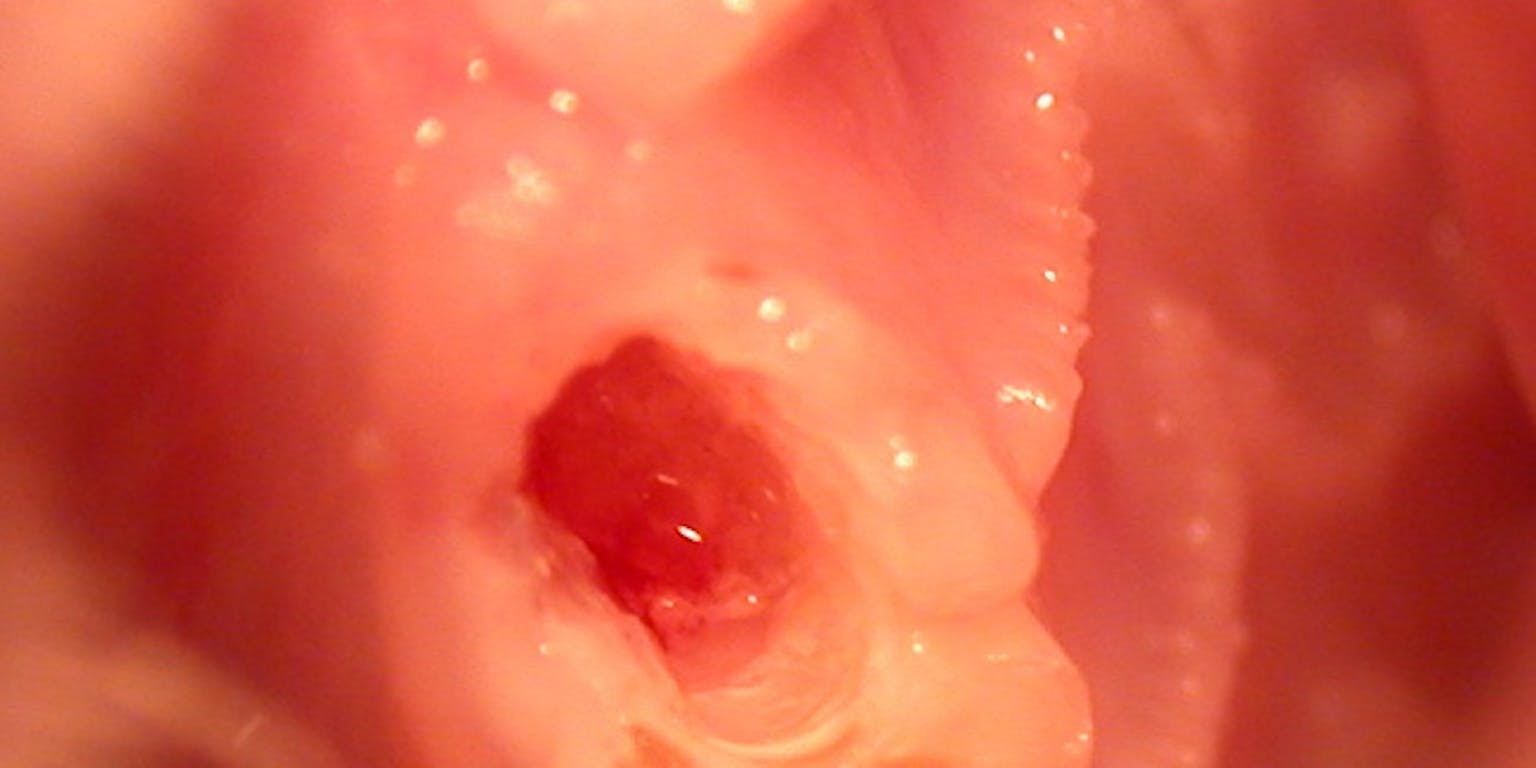

Gat in de tand van een rat. In het gat is het zachte weefsel van de tand zichtbaar, waarin zich de stamcellen bevinden.

Arany PR et al.Twaalf weken later bekeken hij en Mooney het resultaat. Op röntgenfoto’s en onder de microscoop was duidelijk te zien dat er in de behandelde tanden nieuw dentine werd gevormd.